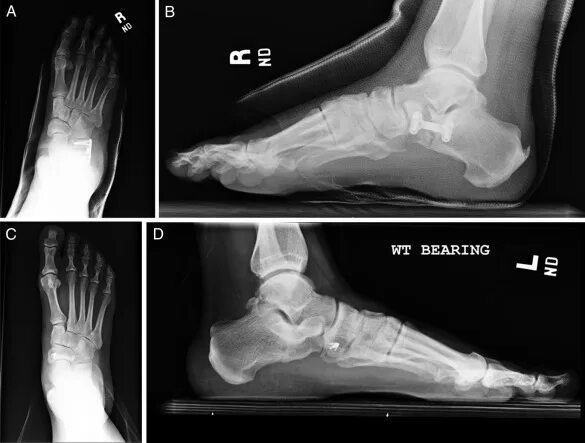

Пяточная остеотомия